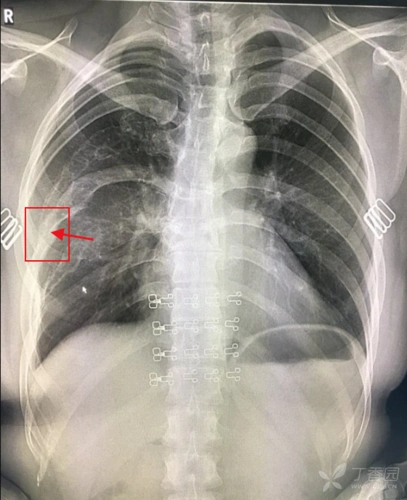

漏斗胸是相对常见的胸廓畸形,占胸廓畸形总数的90%.发病率0.1%-0.